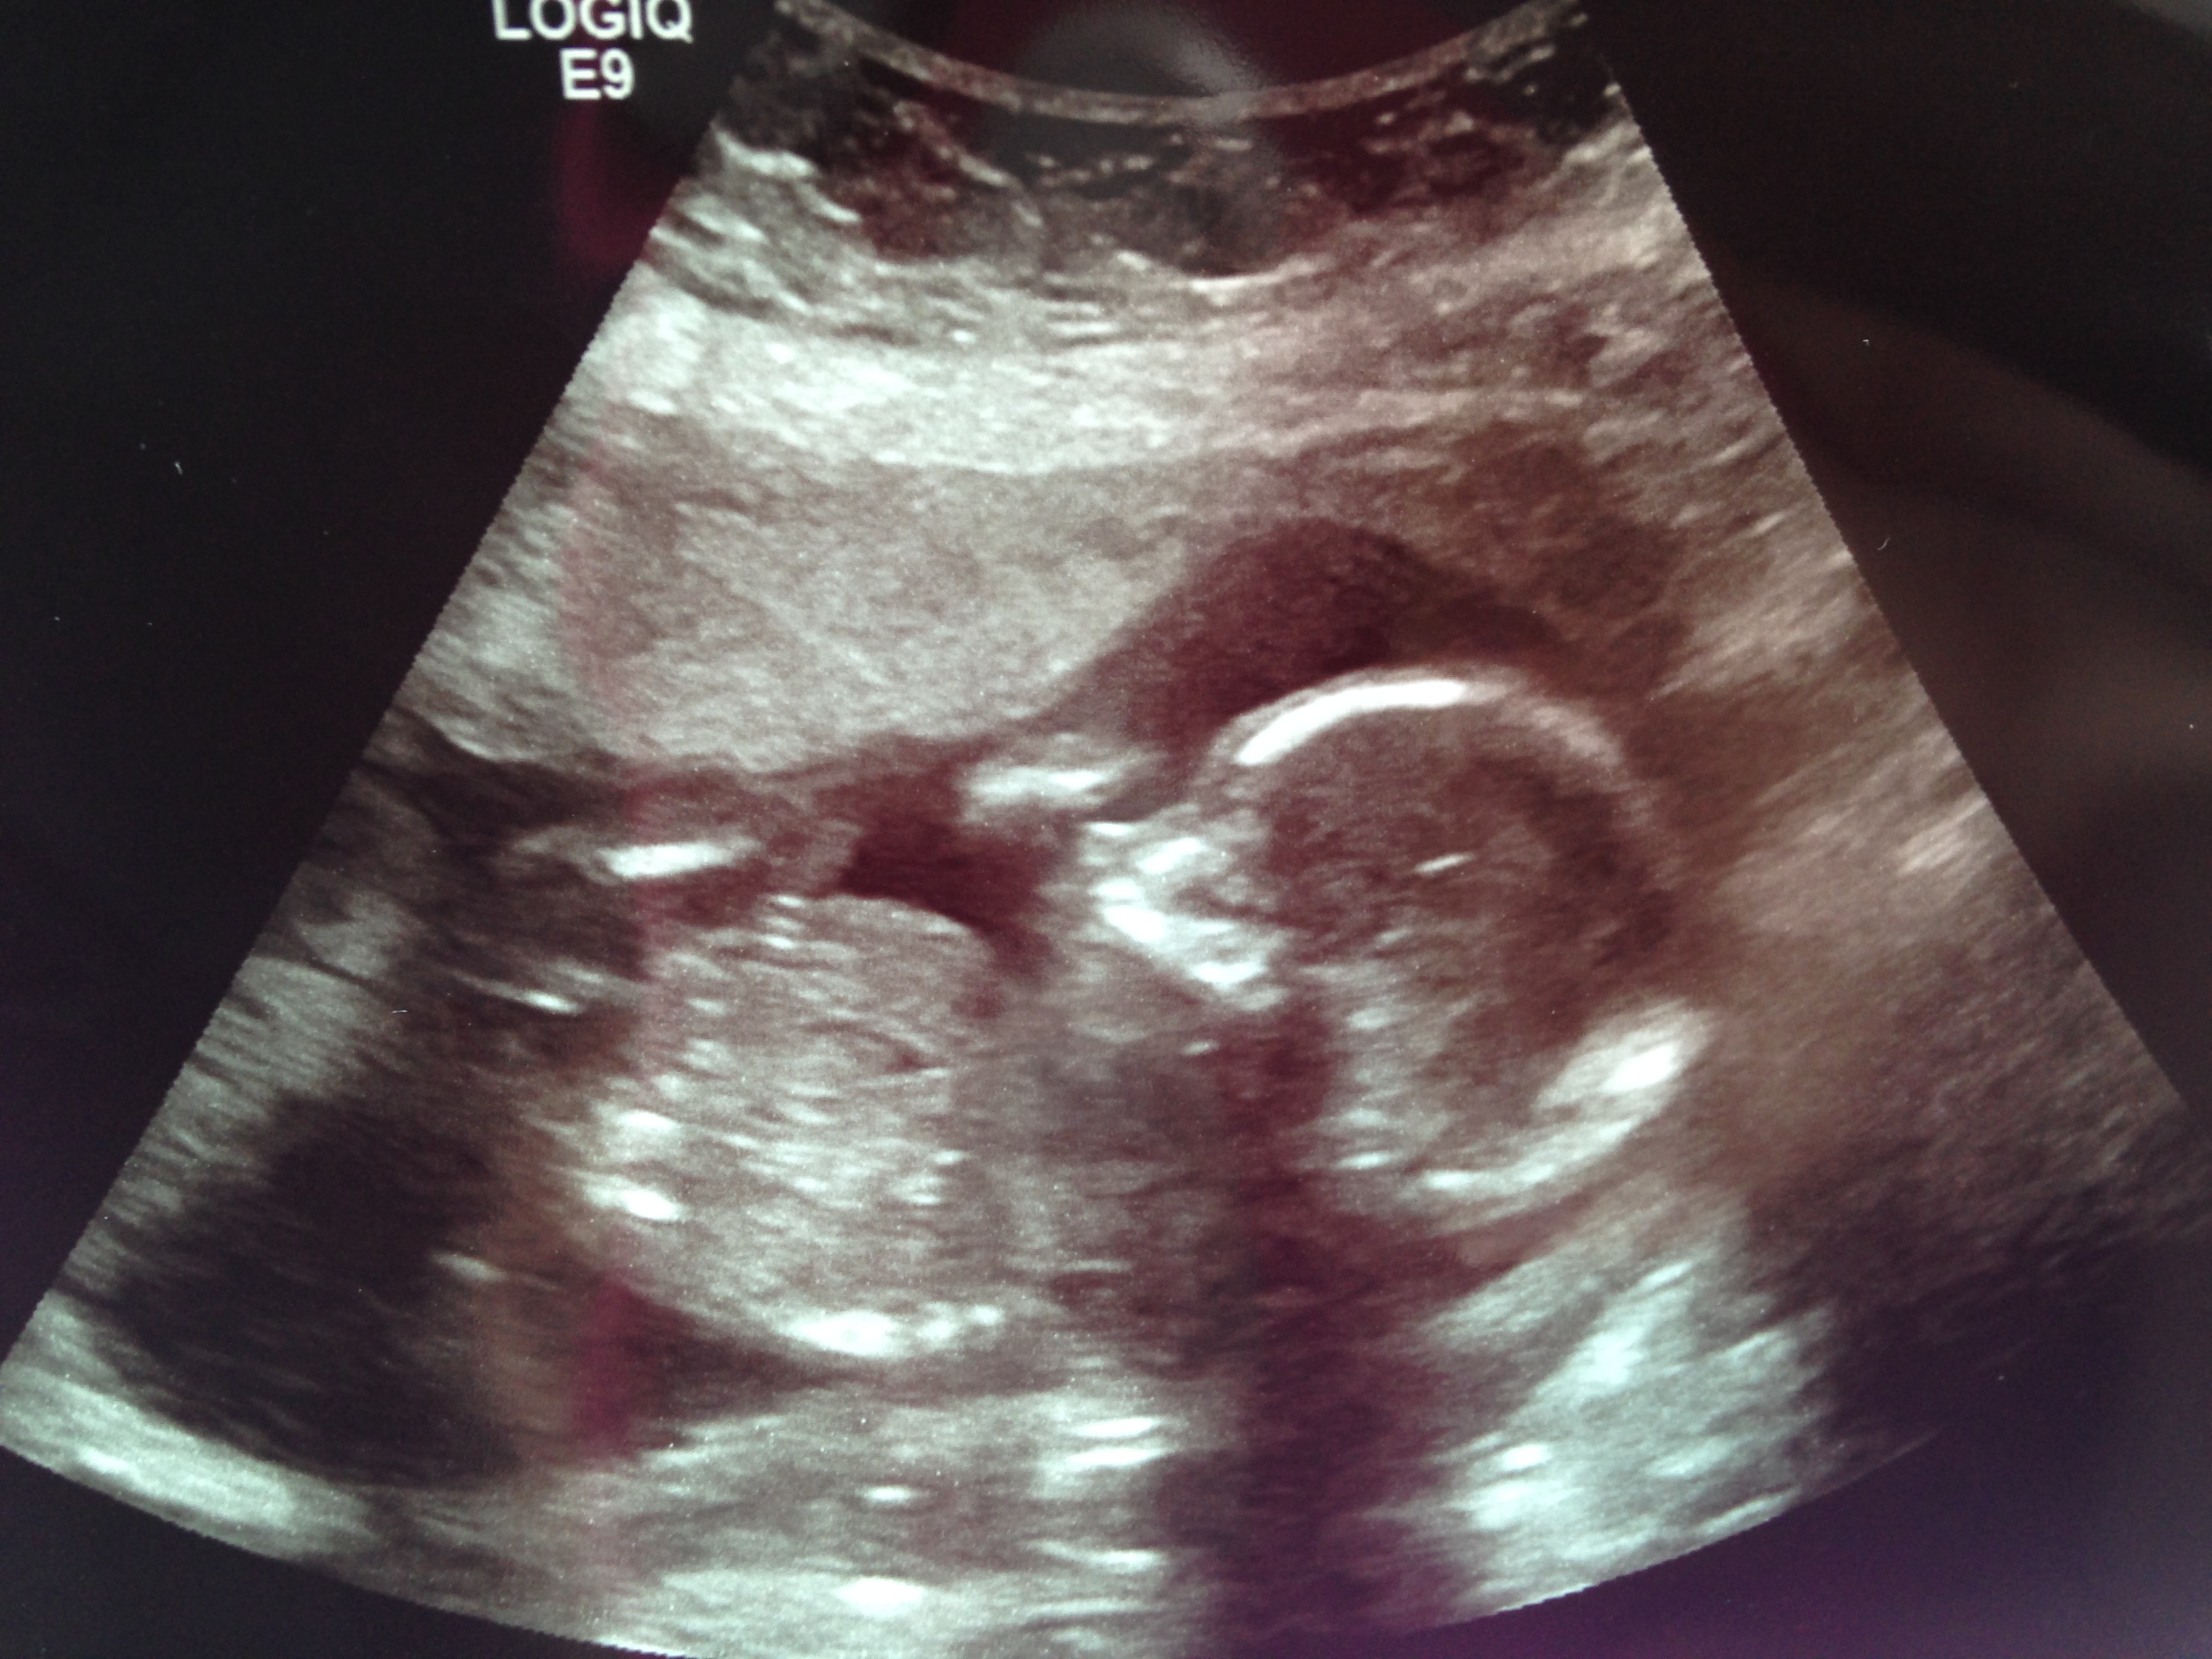

Last Friday was my 19 week ultrasound, also known as the “Big Ultrasound”.

After a few minutes we got to see our baby on the screen.

….healthy baby!

We are so thankful and relived that everything looks good.